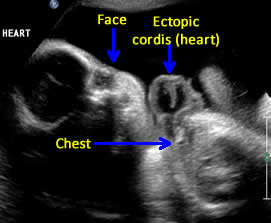

Above. Pentalogy of Cantrell. Case 1. 34 6/7 weeks gestation. Mid-line lower sternum defect with ectopic cordis.

Above. Pentalogy of Cantrell. Case 1. 34 6/7 weeks gestation. Pentalogy of Cantrell showing relationship of ectopic heart to fetal face.